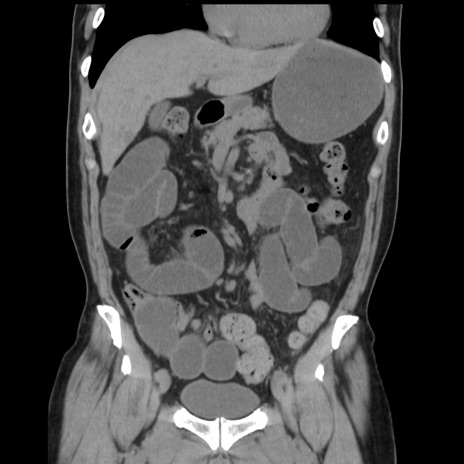

症例16(冠状断像)

【症例】 70歳代男性

【主訴】 腹痛、嘔吐

【現病歴】 約1ヶ月前より間欠的に腹痛と嘔吐あり、当院消化器内科を受診したところCTで多発する肝臓のLDAを指摘され、精査中であった。以降は消化器症状は安定していたが、2日前より嘔気と腹痛があり、同日より排便・排ガスが消失した。改善認めず、 本日、救急外来を受診した。

【既往歴】 大腸ポリープ切除後。

【身体所見】意識清明・会話良好、BT 36.3℃、BP 127/80mmHg、 P 80bpm、腹部:膨満あり、平坦・軟、上腹部正中および下腹部正中に圧痛あり、反跳痛なし、筋性防御なし。

【データ】WBC 7200、CRP 0.77